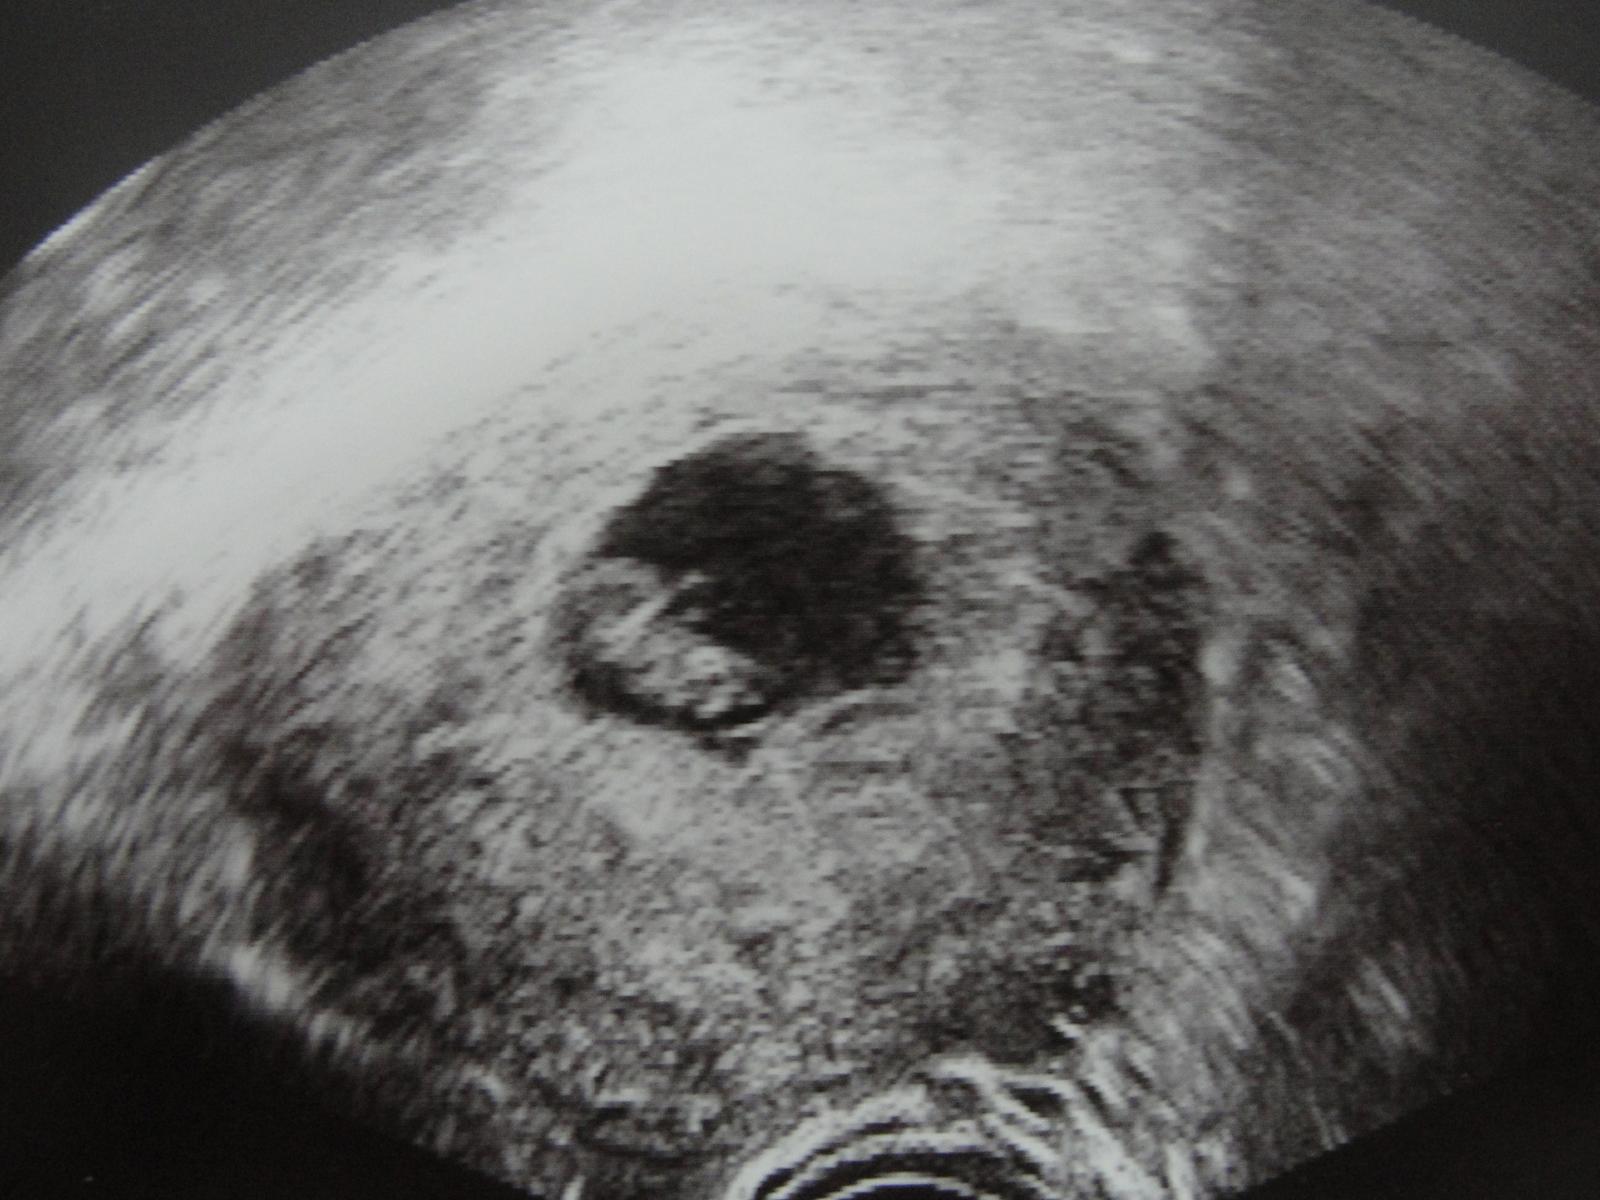

Takže už sme domka a všetko dopadlo na výbornú !!! zodpovedáme 8tt máme 13mm a termín pôrodu 29.7.2013,,, 😵

Pán doktor ked nás zbadal hned povedal,že aký ste veľkí 😵 a srdiečko sme s mm počuli nádherná melódia 😵 😵 😵

@sijust veru môžeš ísť robiť výpočty pôrodu !! presne si to napísala aj tehu kalkulačka po IVF mi to tak vyrátala ,áno krásne vidieť ručičky a to srdiečko ako blikalo a ked nám pustil na chvíľku zvuk no krááása!!!! 🙂 🙂 najkrajšia hviezdička 🙂 a bruško pohladkané 🙂 🙂